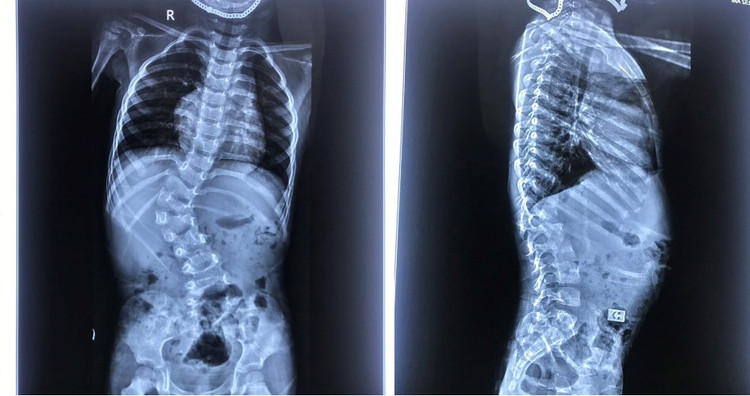

![]() |

| Gù vẹo cột sống ảnh hưởng nghiêm trọng tới sự phát triển của trẻ - Ảnh BVCC |